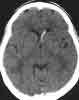

1. What is the rationale behind the decision to orderthe scan?

2. What does the CT scan show?

This patient's presentation was deceptively benign.Many physicians would not have ordered a CT scan inthis setting. Even a patient with minor head trauma whoexperiences a short loss of consciousness might be dischargedwithout a CT scan if the mental status is improvingand the neurologic examination is normal.

Diagnostic clues. Sudden onset of headache suggestsintracranial or subarachnoid hemorrhage, especiallyif the patient experiences syncope or near-syncope. Incontrast to the relatively minor BP elevations that occurin patients with ischemic stroke, intracranial hemorrhageis commonly associated with a profound reactiverise in BP.